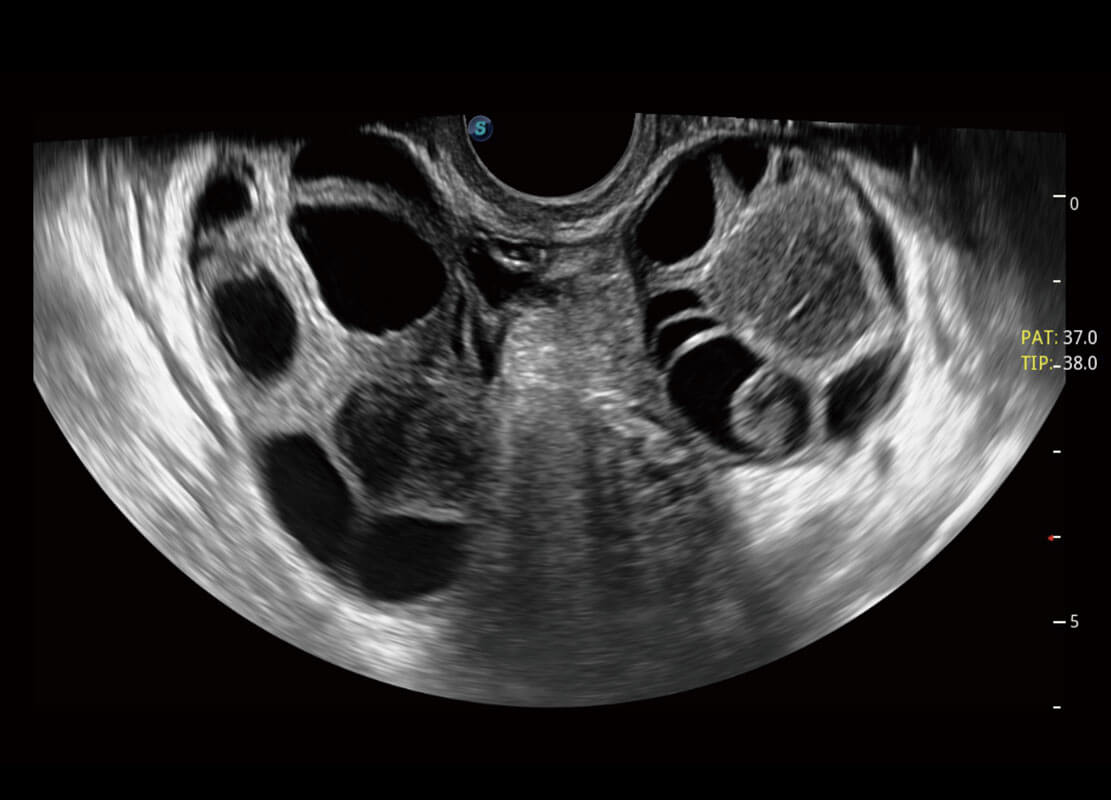

P60优异的图像质量搭载专科探头,在妇科基础疾病的诊断、卵泡生长的监测、输卵管通畅情况的判别等方面为您提供生殖应用方案。

腔内妇科-宫腔分离

腔内妇科-卵巢